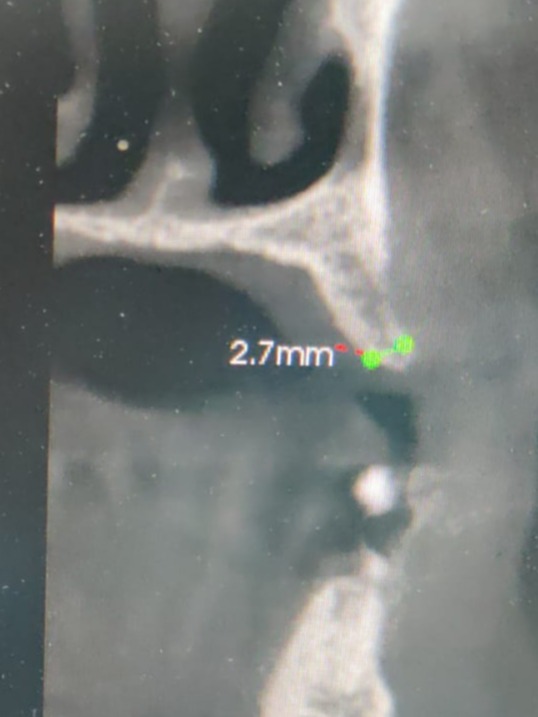

**“I was nervous when I first learned my jawbone was very narrow—just 2.5 mm—and worried about whether an implant would even be possible. Dr. Kedar Bakshi explained the procedure clearly and told me he would be using his special Osseosure system to preserve my bone and make the process more comfortable.

It was really challenging case. Delayed implantation with highly resorbed bone.

It was acid test for osseosure to create osteotomy without fracturing bone. and osseosure did it .

implant went with 40 NCm torque.

Satisfactory x ray.